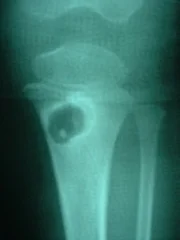

Paciente femenino de 4 años de edad, portadora de HIV, acudió con su representante por mi   consulta, presentando aumento de volumen con signos de rubor y calor en tercio proximal de la pierna izquierda. El laboratorio reporto leucocitosis con elevación de la velocidad de sedimentación globular.

El El estudio radiológico demostró imagen osteolítica en la tibia proximal, procediéndose a la toma de biopsia de la lesión con aguja especial. El diagnóstico histopatológico y bacteriológico fue de osteomielitis crónica por Estafilococo Coagulasa positivo. Fue intervenido quirúrgicamente por el Dr. Alberto A. Martínez Conde,  practicándosele curejate de la lesión con márgenes de resección de aproximadamente

5 mm. Permaneció hospitalizada por 6 semanas con antibiótico terapia parenteral. Recibió tratamiento  por vía oral hasta completar 4 meses. Controlada periódicamente por el Dra. Lisbeth Aurenti (Infectólogo) y el Dr. Alberto A. Martínez Conde. Hasta los momentos 7 años despues, la paciente esta clínicamente curada.